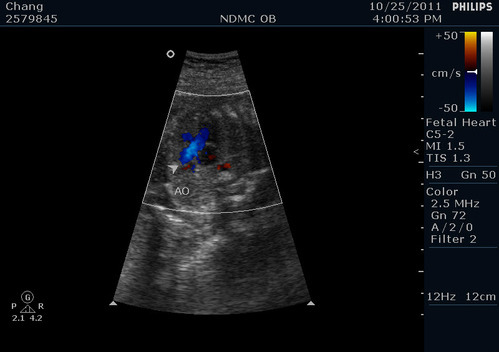

箭頭指的地方是心室中膈~左右心房中間正常沒有破洞

左右心室中間有一個開口等出生之後會自己合起來

紅色的是從心房打到心室的血流

這邊要注意如果紅色中間有藍色的就表示可能有逆流的狀況

這邊醫生看很仔細~因為容易跟主動脈的藍色血流搞混~確定沒有逆流破洞~而且2進2出~正常!